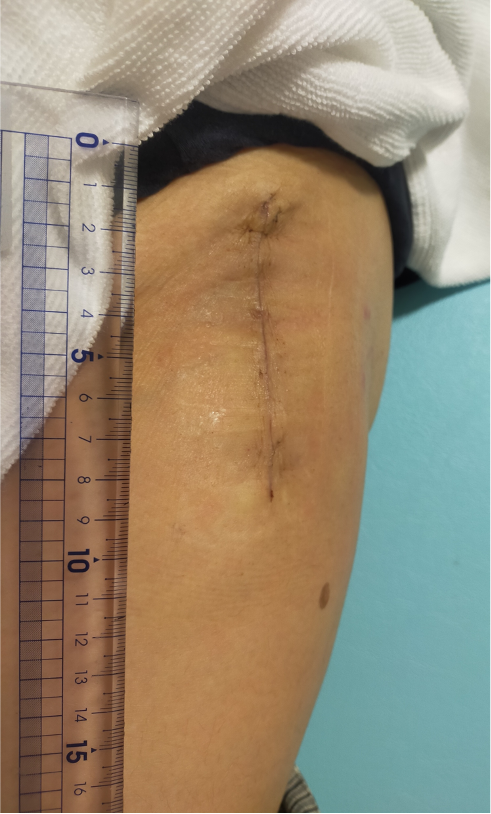

〈キズの大きさ、部位〉

左の太もも前側(約7〜8cm)術後2週の状態